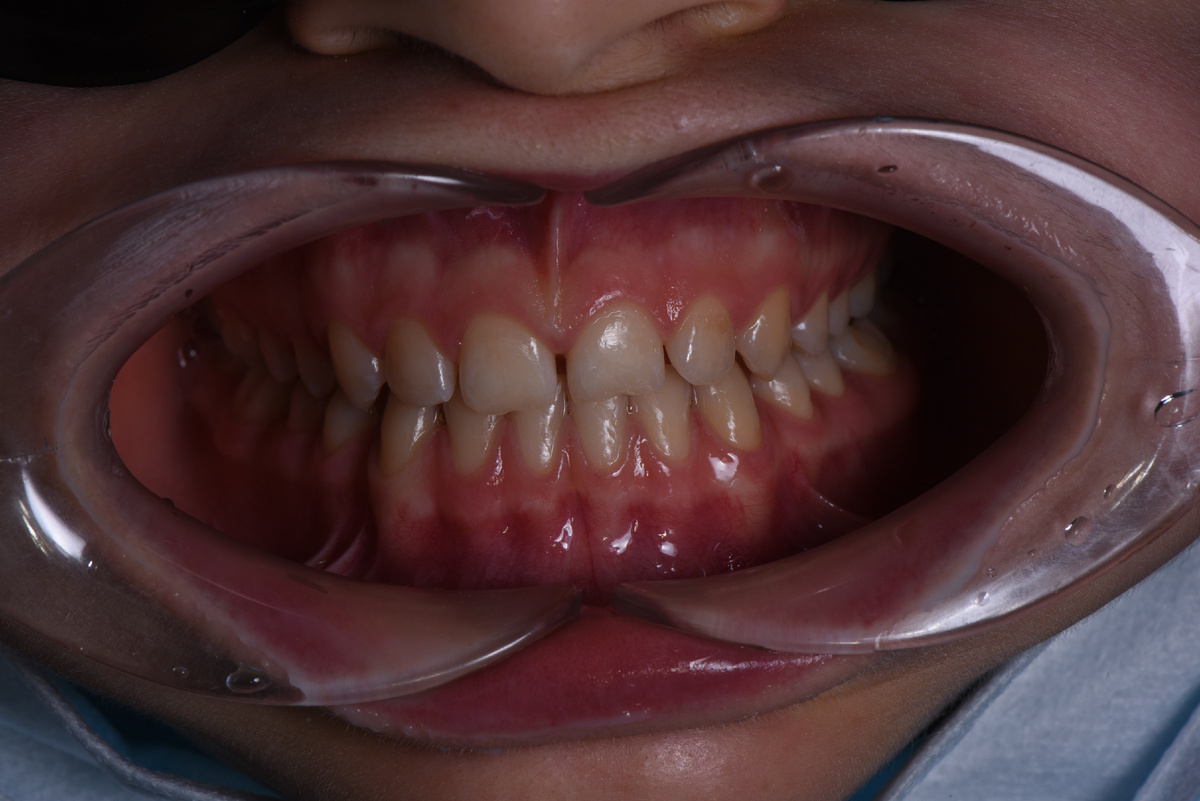

Зубы Тамары небольшого размера, между ними большие промежутки. Кроме того, передние зубы сколотые вследствие травмы👇

Первым делом провели снятие аппаратуры зубного ряда: сняли брекеты, установленные Тамаре в сторонней клинике. Сделали профессиональную гигиену — и вот что увидели👇